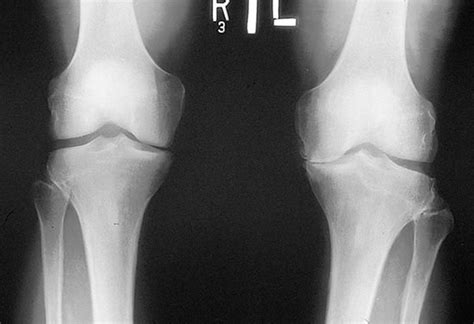

When a radiologist examines an X ray of healthy knee, they are looking for specific visual indicators that confirm the joint is functioning correctly. The knee is a complex hinge joint involving the femur (thigh bone), the tibia (shin bone), and the patella (kneecap). In a perfectly healthy state, the interaction between these bones is precise and well-lubricated.

Key anatomical markers of a healthy knee include:

- Clear Joint Space: This is perhaps the most important feature. On an X-ray, you will see a dark, uniform gap between the bones, representing the cartilage. A consistent space indicates that the articular cartilage is thick and healthy.

- Smooth Bone Contours: The edges of the femur and tibia should appear smooth and continuous without any jagged edges, bone spurs (osteophytes), or irregular growths.

- Proper Alignment: The bones should be stacked in a way that distributes weight evenly across the joint, preventing excessive pressure on one side of the knee.

- Patellar Positioning: The kneecap should sit neatly within the trochlear groove of the femur, showing no signs of tilting or shifting.

To obtain a clear X ray of healthy knee, patients are usually asked to stand. This is crucial because it allows the doctor to see the knee under the stress of body weight, which reveals how the joint behaves during movement. A standard series often includes an Anterior-Posterior (AP) view, a lateral view, and sometimes a sunrise view to examine the patellofemoral joint.